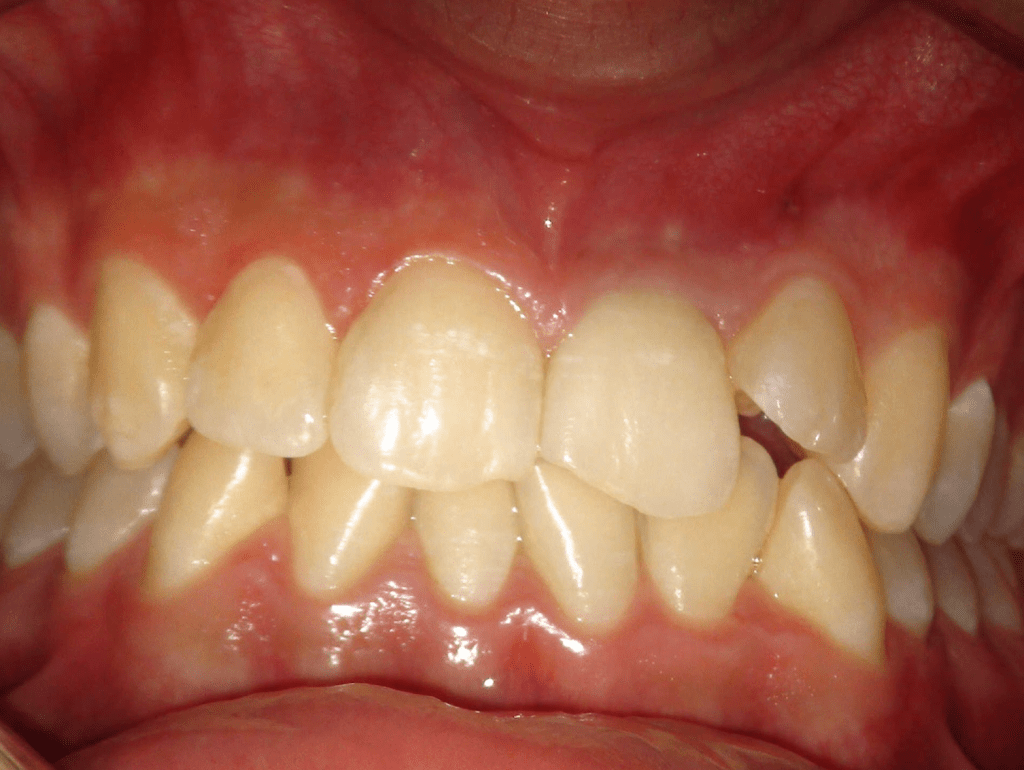

Autotansplantes

CALCIFICADOS

Incisivo superior Endo-perio

Incisivo superior trauma

Premolar calcificado lesion